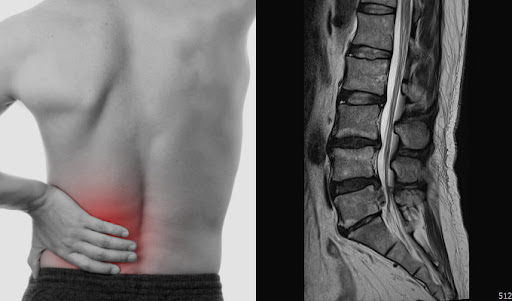

4. 근골격계 질환 (퇴행성 관절염, 허리디스크, 오십견 등)

중년기 이후에는 노화로 인해 근육량이 줄고 관절과 척추의 유연성이 떨어지면서 다양한 근골격계 질환이 나타납니다. 특히 체중 증가와 잘못된 자세, 무리한 운동 등이 이러한 질환의 주요 요인입니다.

주요 질환

퇴행성 관절염: 관절 연골이 닳아 없어지면서 통증과 염증이 발생. 무릎, 손가락, 고관절 등에 흔합니다.

허리디스크: 추간판이 탈출하면서 신경을 압박해 통증, 저림 등을 유발.

오십견(유착성 관절낭염): 어깨 관절의 움직임이 제한되고 극심한 통증이 동반됩니다.

증상

관절의 뻣뻣함, 아침에 특히 심함

관절 사용 시 통증 증가

허리 통증, 다리 저림

어깨 통증 및 움직임 제한